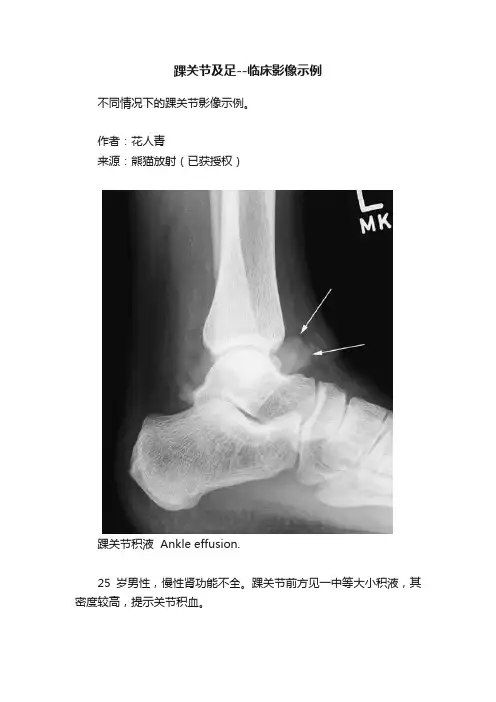

作者:***来源:熊猫放射(已获授权)踝关节积液 Ankle effusion.25岁男性,慢性肾功能不全。

踝关节前方见一中等大小积液,其密度较高,提示关节积血。